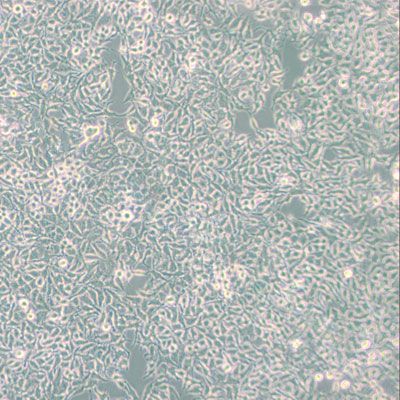

肺動(dòng)脈高壓(PAH)是指肺動(dòng)脈壓力異常升高的一種血流動(dòng)力學(xué)和病理生理狀態(tài)。PAH病理變化包括肺血管內(nèi)側(cè)肥大、內(nèi)膜增生和纖維化、原位血栓形成、外膜增厚伴隨中度血管周圍炎癥細(xì)胞浸潤、叢狀擴(kuò)張性病變,肺血管重塑(過度細(xì)胞增殖、纖維化和血管壁細(xì)胞凋亡或程序性細(xì)胞死亡減少、炎癥、某些生長因子的代謝和失調(diào))使血管部分閉塞,肺血管阻力增加,導(dǎo)致進(jìn)行性右心衰竭和功能衰退,甚至死亡。本公司經(jīng)頸背部皮下注射MCT溶液誘導(dǎo)PAH模型。

大鼠經(jīng)頸背部單次皮下注射MCT溶液誘導(dǎo)PAH模型,期間大鼠自由進(jìn)食及飲水,動(dòng)物表現(xiàn)為體重明顯降低。